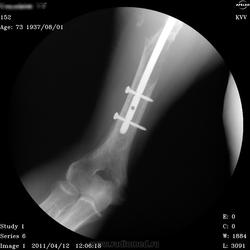

Пол пациента: Мужской пол Тип патологии: Злокачественное новообразование Область исследования: Скелетно-мышечная система Методы исследования: Rg ID:13335 Втр, 12/04/2011 - 07:24 #1 Vikkur Не на сайте Был на сайте: 4 года 8 месяцев назад Зарегистрирован: 24.09.2009 - 14:34 Публикации: 1749 Rv ...Приложения: Виктор. Втр, 12/04/2011 - 21:11 #2 tatyana Не на сайте Был на сайте: 4 года 1 месяц назад Зарегистрирован: 24.06.2009 - 08:33 Публикации: 2090 мтс множественные, возможно - имплантационные, резекция - сомнительна, вероятнее - биопсия "самоуверенность дилетантов - предмет зависти профессионалов" Чт, 14/04/2011 - 03:30 #3 Vikkur Не на сайте Был на сайте: 4 года 8 месяцев назад Зарегистрирован: 24.09.2009 - 14:34 Публикации: 1749 Вы полностью правы принес сегодня снимки за 2009 - после операции.Приложения: Виктор.

мтс множественные, возможно - имплантационные, резекция - сомнительна, вероятнее - биопсия

Вы полностью правы принес сегодня снимки за 2009 - после операции.